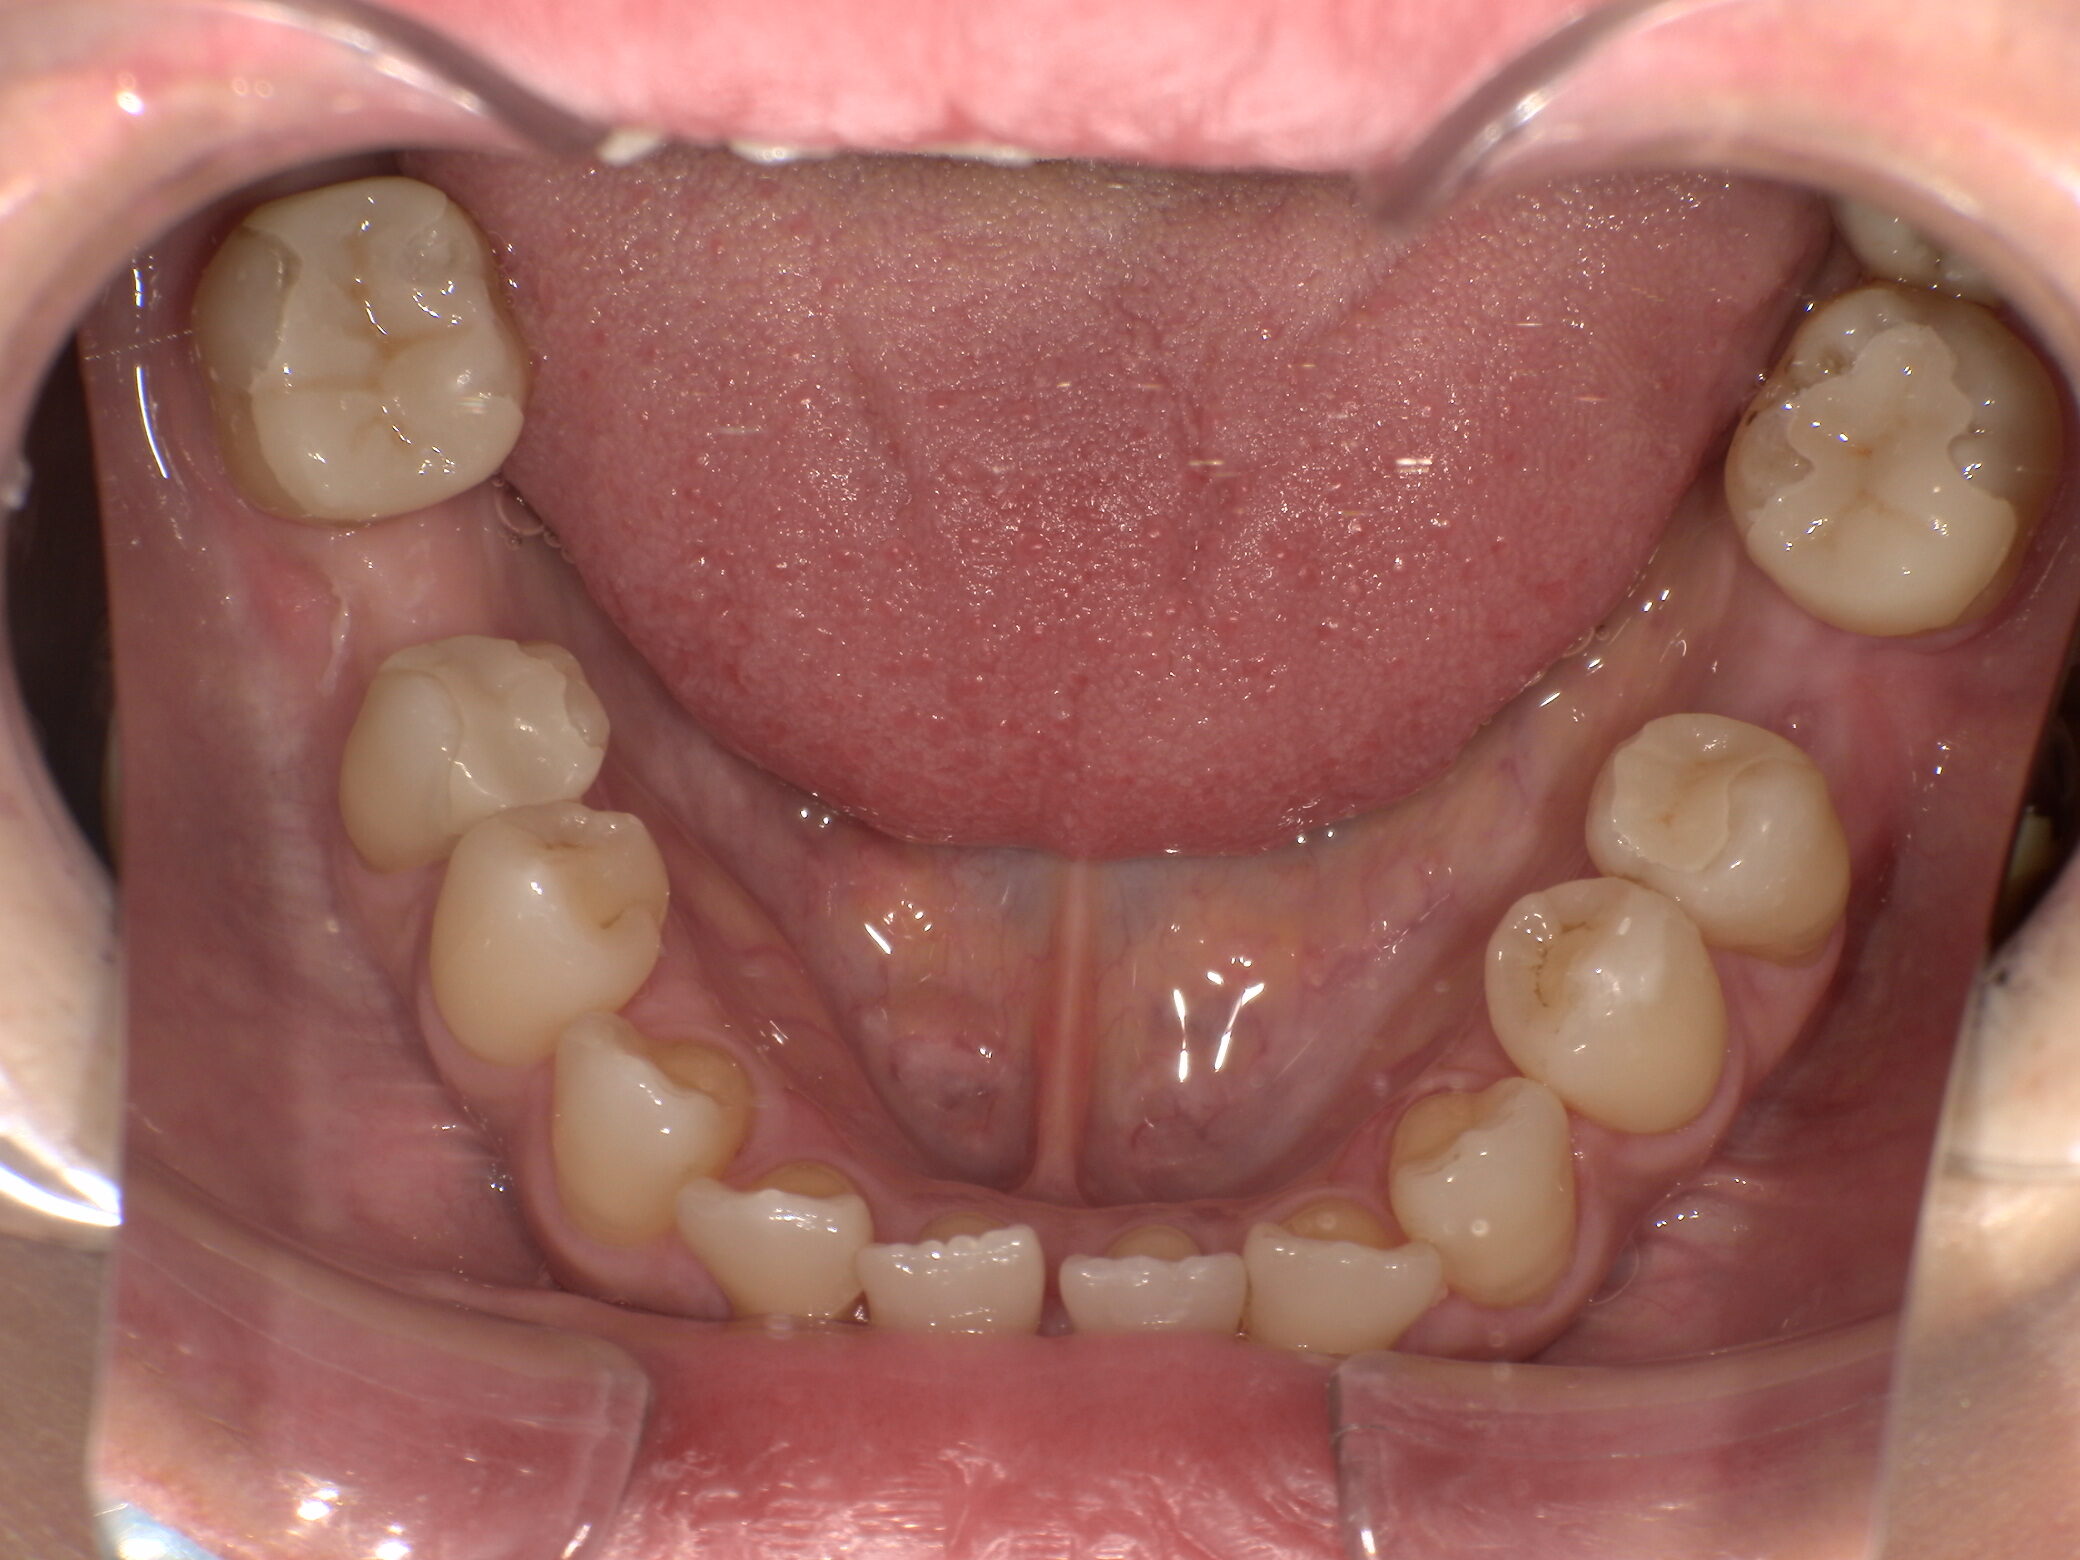

治療前 ![]() |

拝見したところ、34・36・46に金属修復物が装着されており、周囲には二次う蝕と金属特有の色調不調和が認められました。歯質の残存量は十分で、被せ物ではなくインレー修復が可能な状態でした。審美性の改善に加え、金属アレルギーの観点からもメタルフリー治療が適応と判断しました。 |